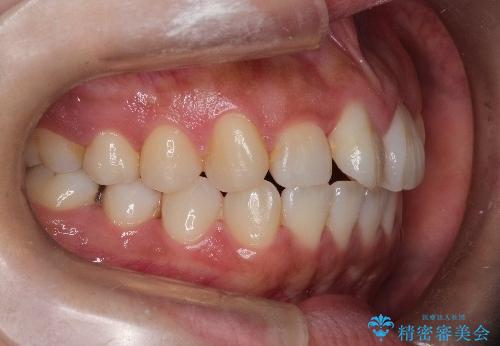

【引っ込んだ前歯が気になる、真ん中の線も揃えたい】インビザライン症例

- 前歯の歯並びの改善を希望され来院された患者様です。

初診時の歯並びの状態としては、上下ともに全体に及ぶの中等度のがたつき(叢生)があり、全特に左上の前歯は1本だけ引っ込んでいる状態でした。

抜歯は行わず上顎の奥のスペースを利用して歯をスライドする方法の他に歯列弓の拡大やディスキング(歯と歯の間の隙間を作る処置)を行い叢生を改善しました。

歯の大きさの不揃いが原因の正中のズレは、ディスキング量を調整することで合わせました。